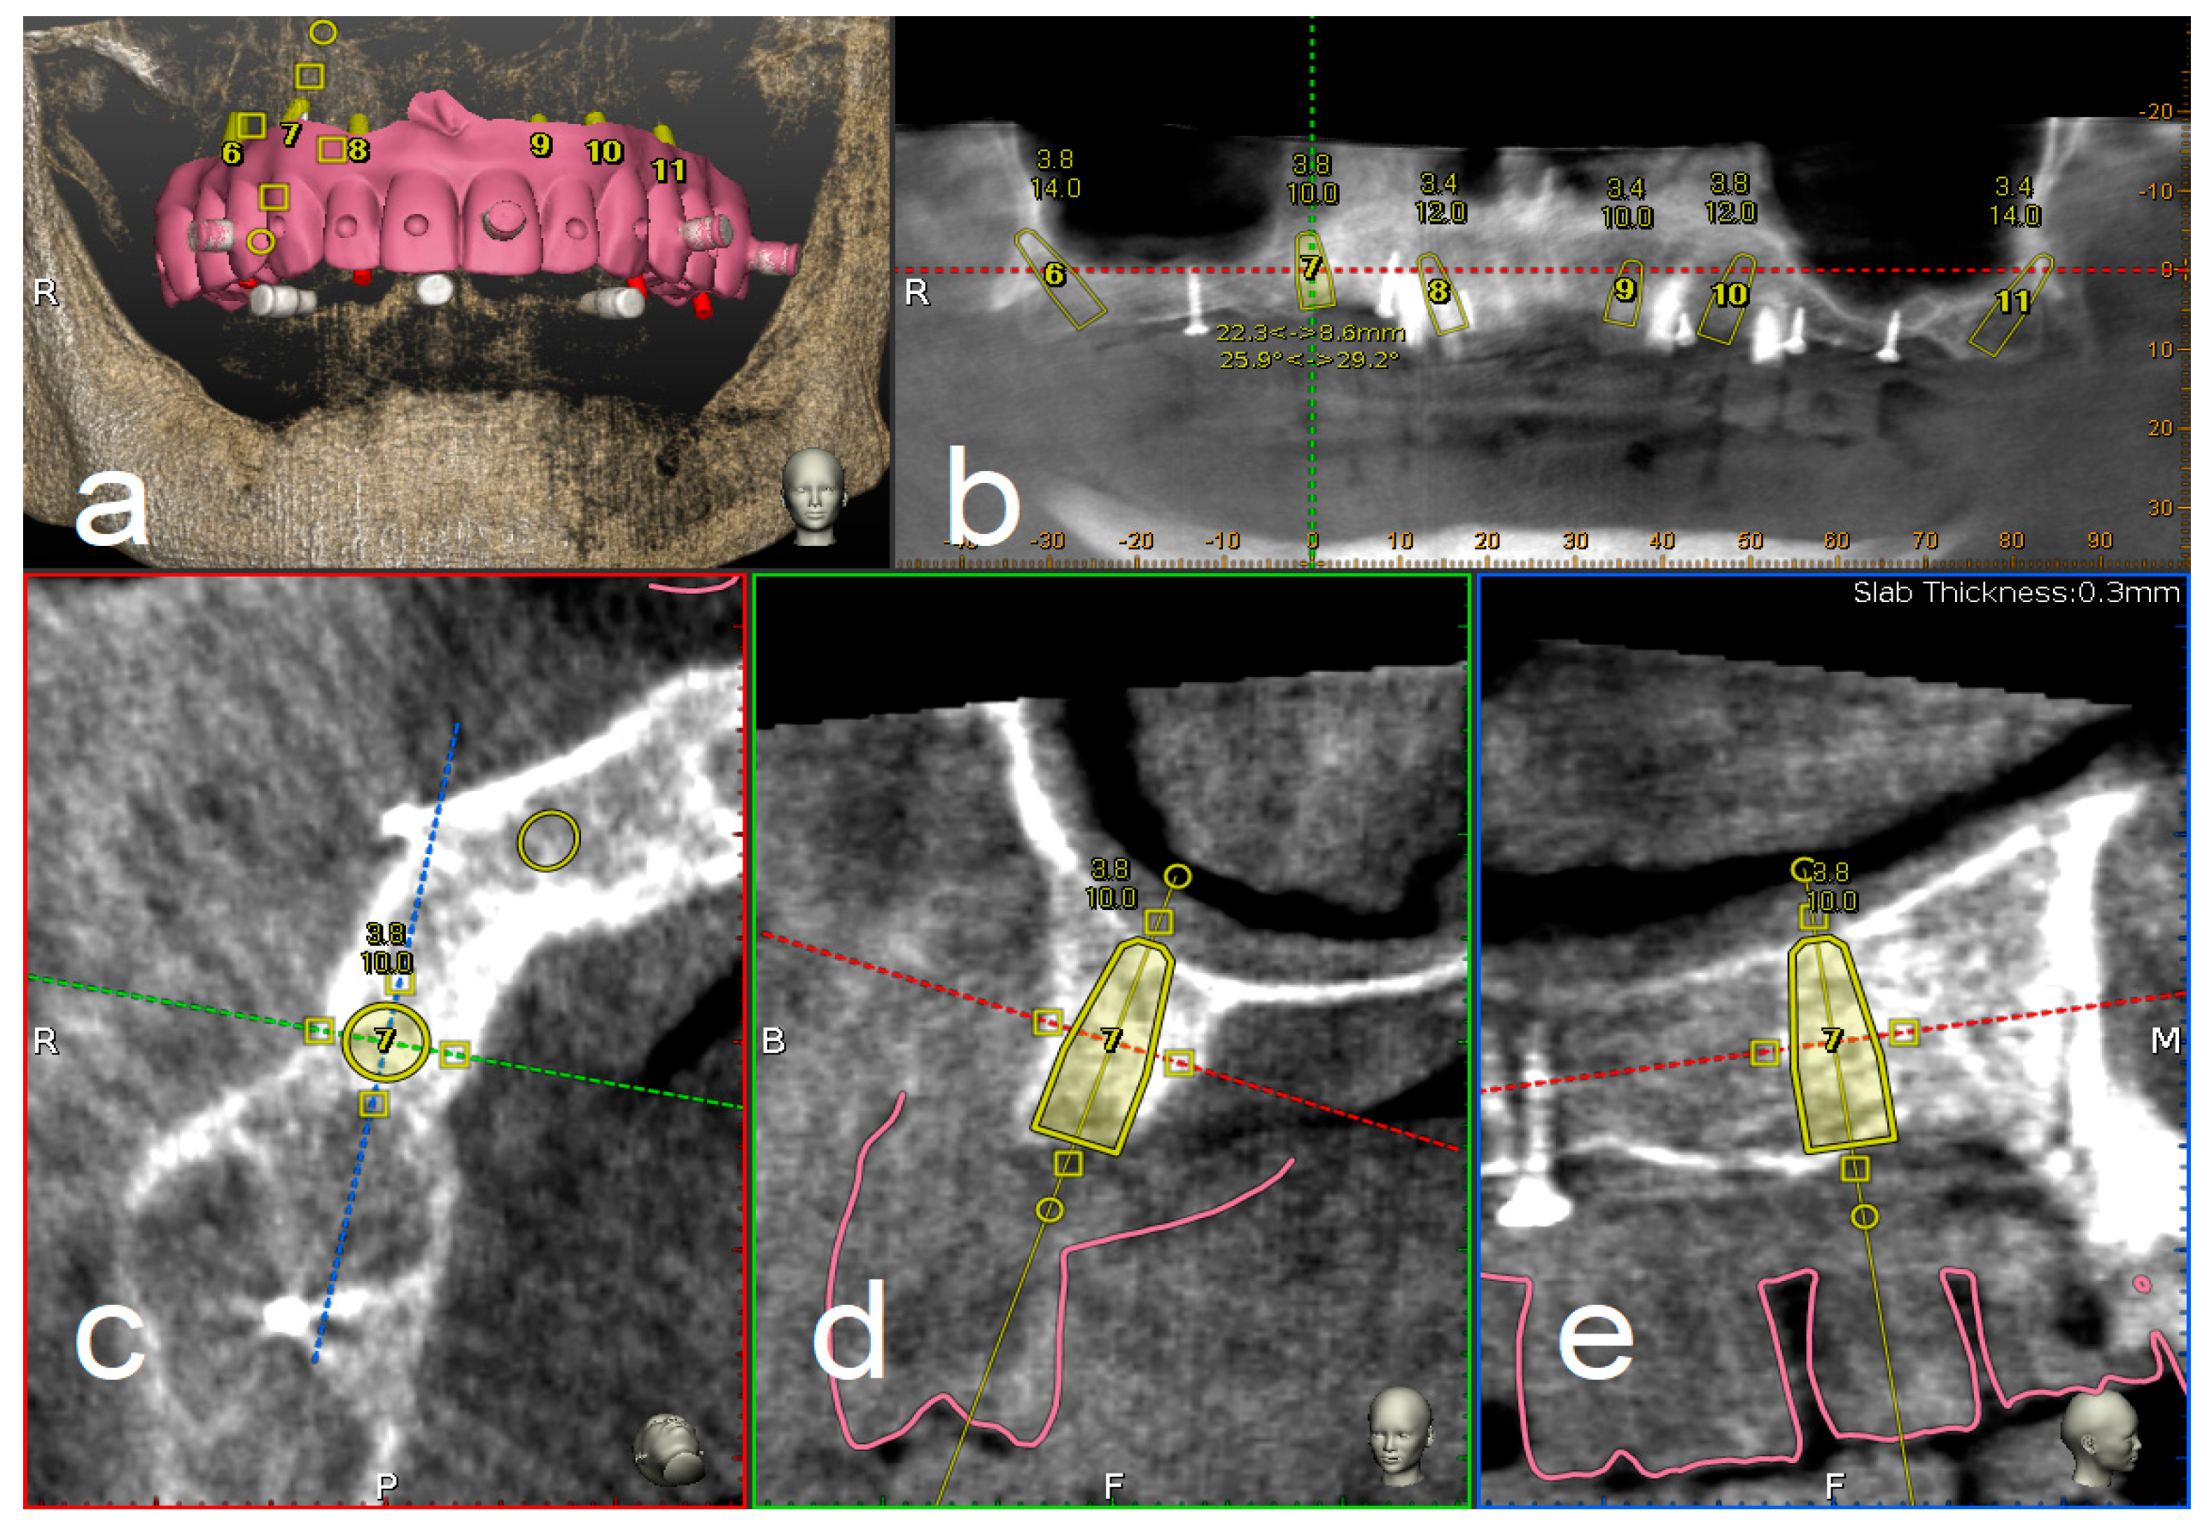

A CBCT (Scanora 3Dx) and an intraoral surface scan (IOS) were taken on each patient. An ideal virtual wax-up of teeth was completed by Lab Technician. Both DICOM files from CBCT and stereolithography (STL) files from the IOS were matched in Navident software and semi-automatically superimposed to residual teeth (or in toothless cases, using reference points in the wax-up) using the provided mesh-to-image registration tool. In addition, the STL files of the final teeth set-up were matched above previous IOS files of the baseline oral conditions and displayed in Navident software to perform prosthetically driven implant planning (Figure 1).

Figure 1.

Implant planning using stereolithography (STL) files as reference for a prosthetic driven implantation (a). Panoramic (b), axial (c), bucco-lingual (d), and parasagittal (e) view.